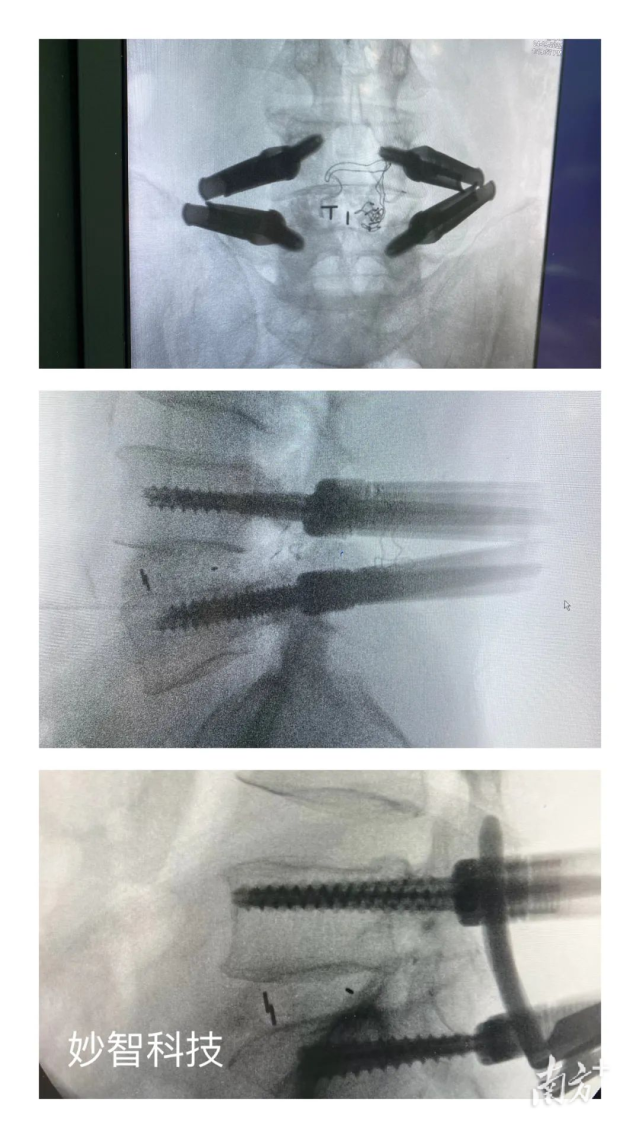

妙智科技研發(fā)的骨科機(jī)器人在臨床中試驗

由於新型醫(yī)療器械壹般研究周期較長,目前,妙智科技研發(fā)的骨科機(jī)器人仍在臨床試驗階段。截至2022年底,妙智科技已經(jīng)完成了近50例臨床病例,預(yù)計今年計劃將完成取證並開始售賣。